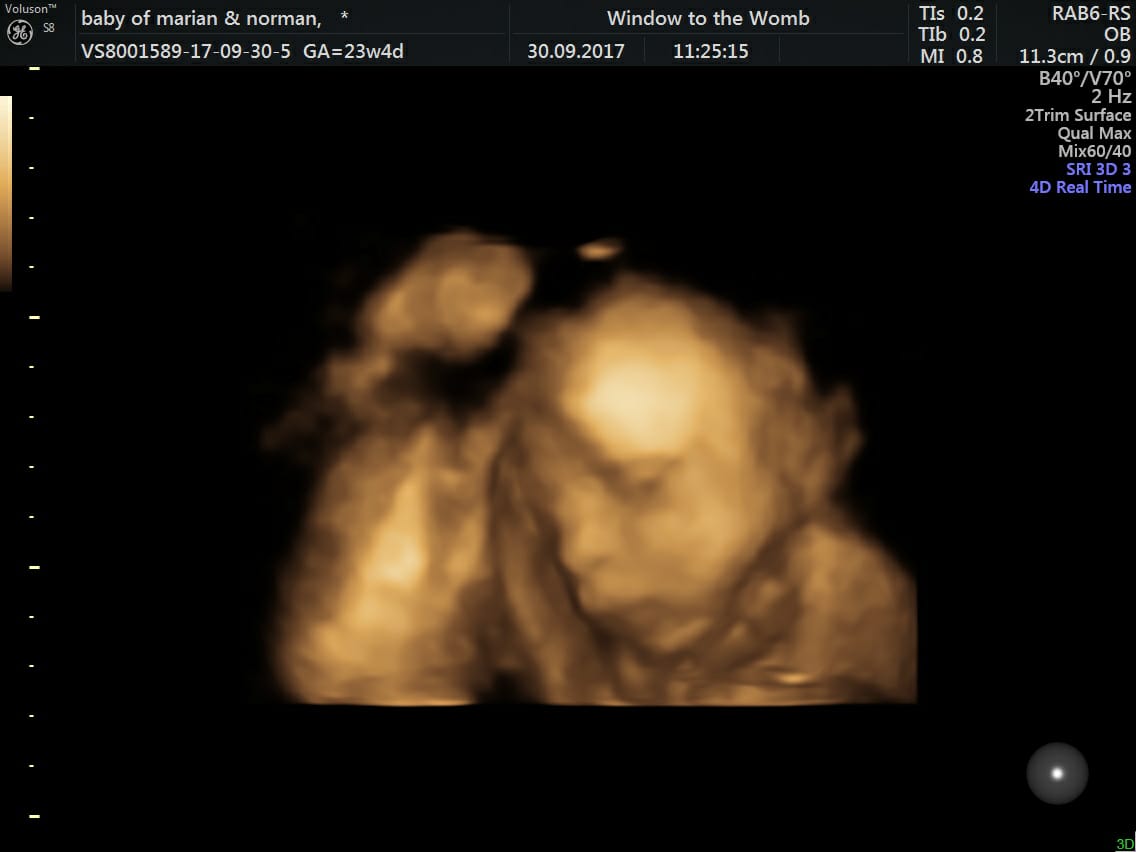

Amazing Story of Baby Jack; Born With One Hand

Say Hello to Baby Jack…The Gorgeous Baba We Scanned At Our Belfast Clinic!

We recently welcomed Mummy Marian and family into our Belfast clinic. This was so they could see Baby Jack in a 4D scan. However his circumstances were just a little bit different…

Parents Marian and Norman attended their 20-week scan at the hospital to unsuspectingly find concerns with baby Jacks’ heart. After returning for another scan at 23 weeks, they couldn’t get the view of Jacks’ heart they needed…but discovered an absent left hand. Marian had planned to visit us at Window to the Womb for a scan at 28 weeks, but after discovering the possible heart issues, decided they needed reassurance as soon as possible. They joined us 3 days later, mainly to see if baby was okay through our technology.

Baby Jacks’ 4D Scan at 23 Weeks

How gorgeous?

“We really are thankful of your team in Belfast as what was the most concerning days; the scan with WTTW gave me a little hope. When I was told about the absent left hand at 23 weeks I went onto shock as I thought the man had got it wrong. But 2 days later and 2 days of thinking, then seeing the baby 4D put my mind at ease.” – Marian B.

Marian got in touch recently and gave us the wonderful news…the heart consultant had given Jack the all clear at 28 weeks! He was born happy and healthy on the 17th January, weighing 7lbs 4 oz. Although his left hand is absent, he is missing less than expected with more of a wrist; this means he will have more support.